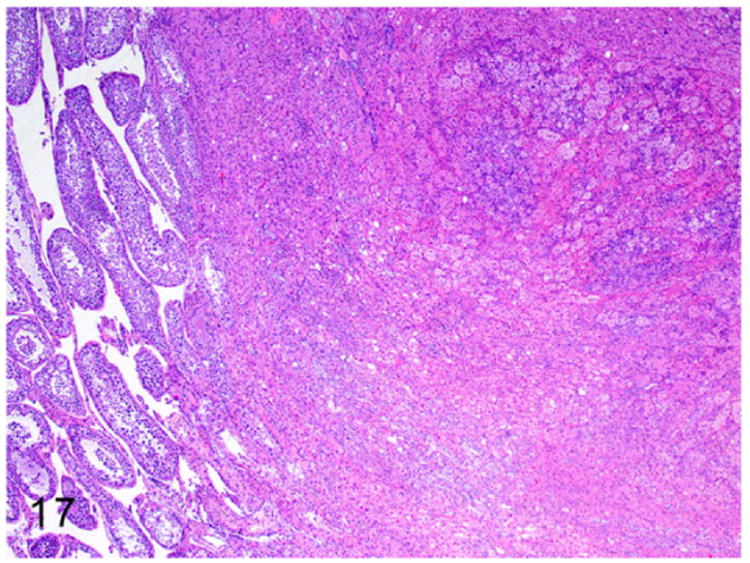

Interstitial cell or Leydig cell tumors have been reported in a 5-year old male ferret.7 Interstitial cells of the testis are located between the seminiferous tubules and are responsible for synthesis of androgens in male ferrets. On gross examination these neoplasms are firm, yellow to orange, and nodular to multinodular in appearance. Microscopically, the expansile, poorly demarcated, and invasive (Fig. 17) neoplasm is composed of polyhedral neoplastic cells. The neoplastic cells are arranged in solid sheets and separated by fine fibrovascular connective tissue. The well-differentiated neoplastic cells have indistinct cell borders and moderate amounts of pale eosinophilic foamy vacuolated cytoplasm. Nuclei are large, oval to round, with finely stippled chromatin and 1-2 prominent nucleoli (Fig. 18). Mitotic figures are rare.

Figure 17.

Interstitial cell tumor, testicle, ferret. An expansile poorly demarcated neoplasm compresses the adjacent seminiferous tubules (on the left). HE.